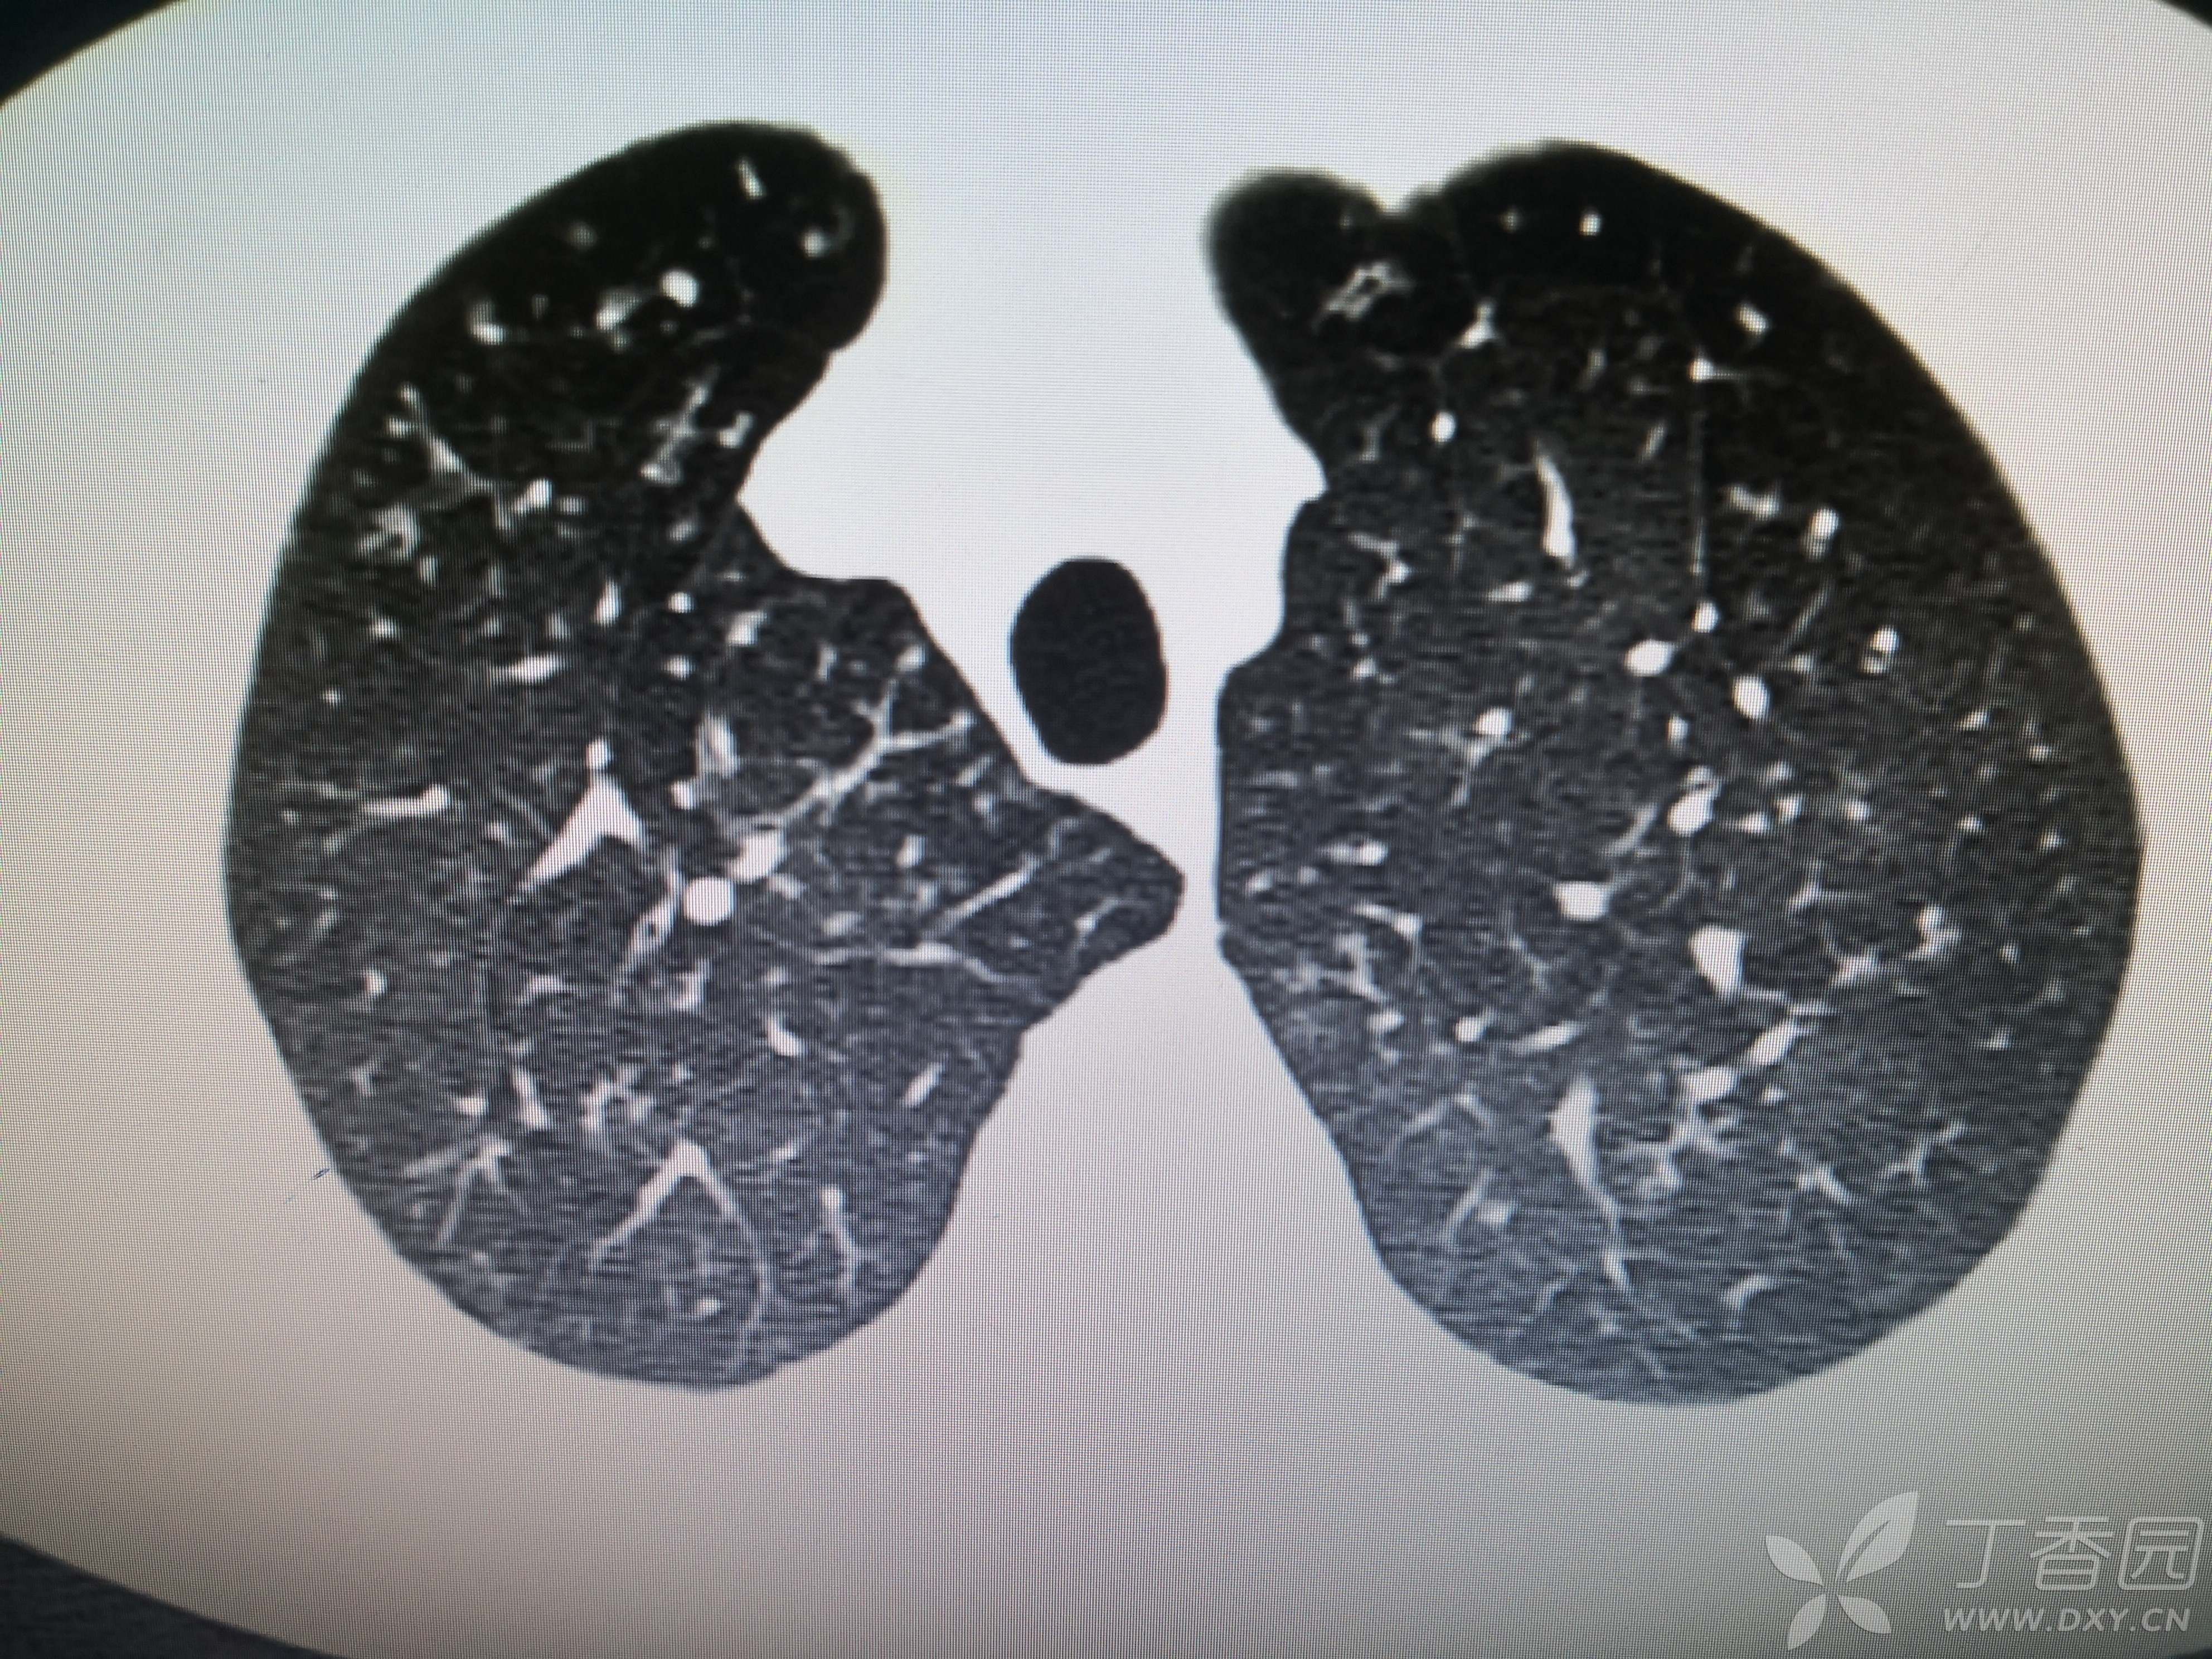

患者性别:女

患者年龄:54岁

简要病史:反复咳嗽、咳脓痰40余年,气喘10年,加剧2周。

体格检查:SpO2:72%,双中下肺闻及中小湿啰音。

辅助检查:见图

临床诊断:支气管扩张并感染

治疗经过:哌拉西林他坐巴坦联合左氧氟沙星抗感染